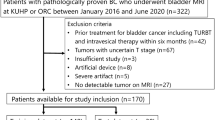

This retrospective study involved analysis of MR images from 169 patients with cervical cancer stage IB–IVA captured; among them, diffusion-weighted (DW) images from 144 patients were used for training, and another 25 patients were recruited for testing. A U-Net convolutional network was developed to perform automated tumor segmentation. The manually delineated tumor region was used as the ground truth for comparison. Segmentation performance was assessed for various combinations of input sources for training. ADC radiomics were extracted and assessed using Pearson correlation. The reproducibility of the training was also assessed.